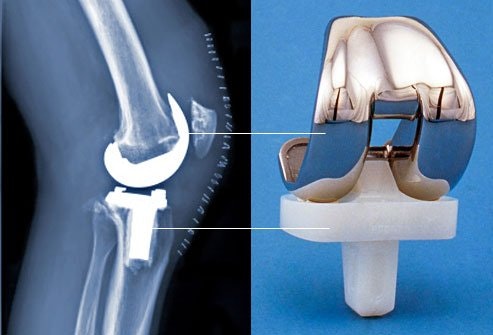

Meanwhile, AAOS figures indicate that in 2010 more than 650,000 knee replacement procedures were performed, with about 90 percent involving total knee replacement.

AAOS estimates from 2014 show that 4.7 million Americans now live with an artificial knee and 2.5 million have an artificial hip.